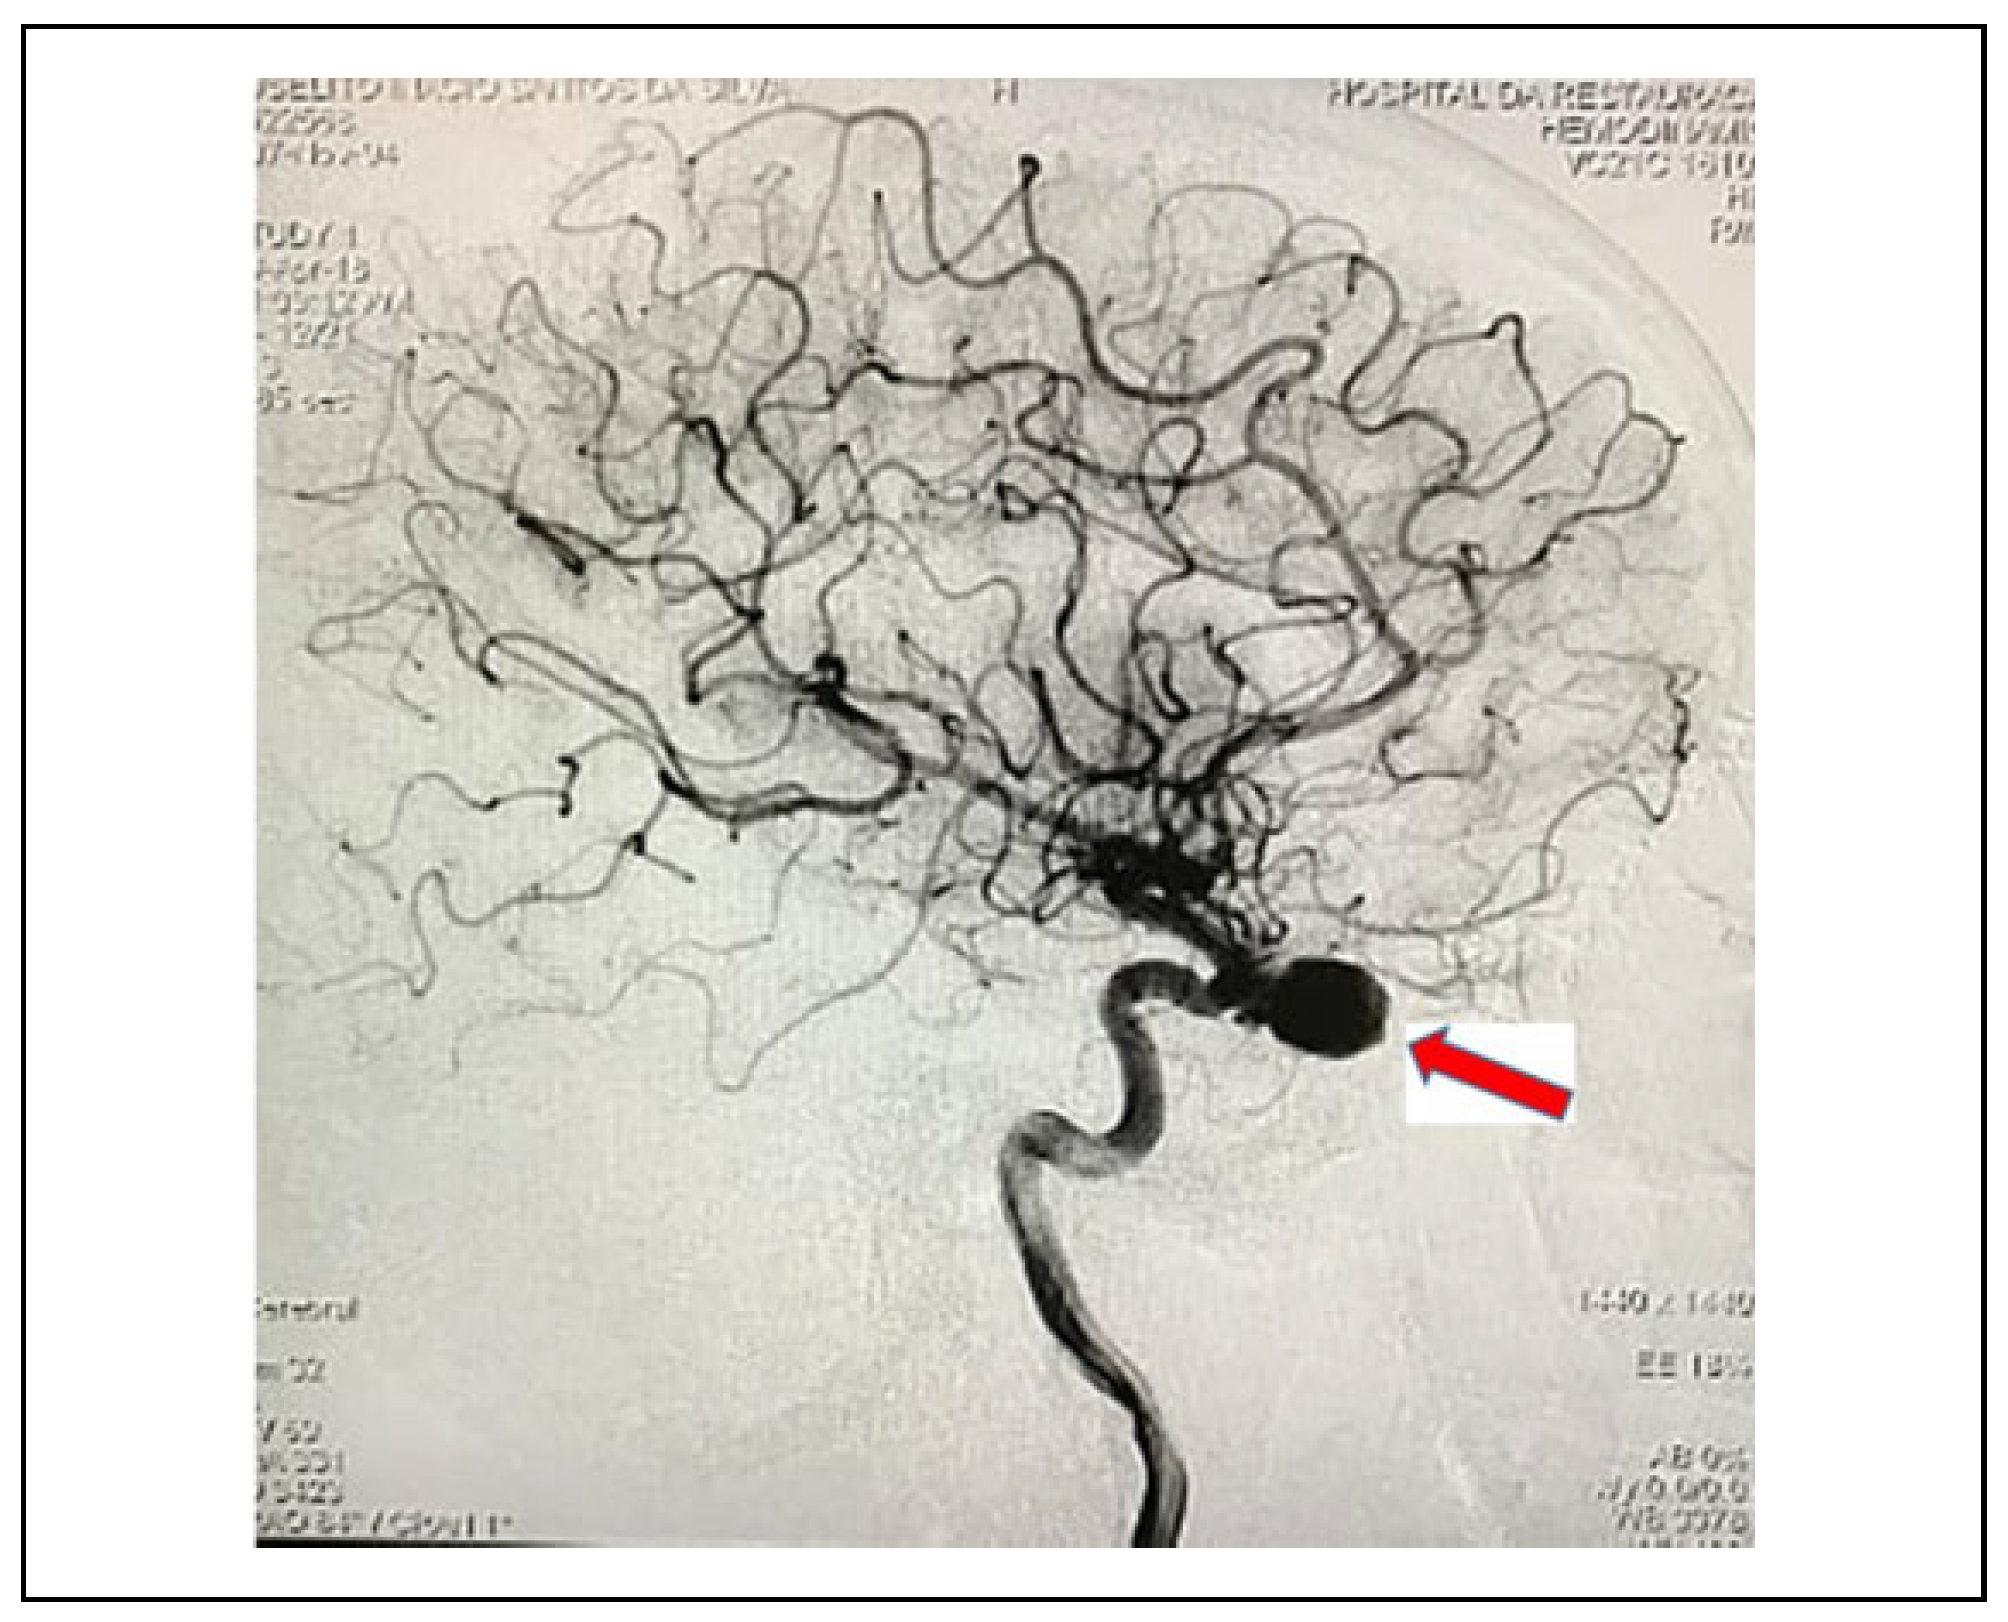

Case 1

Case 2